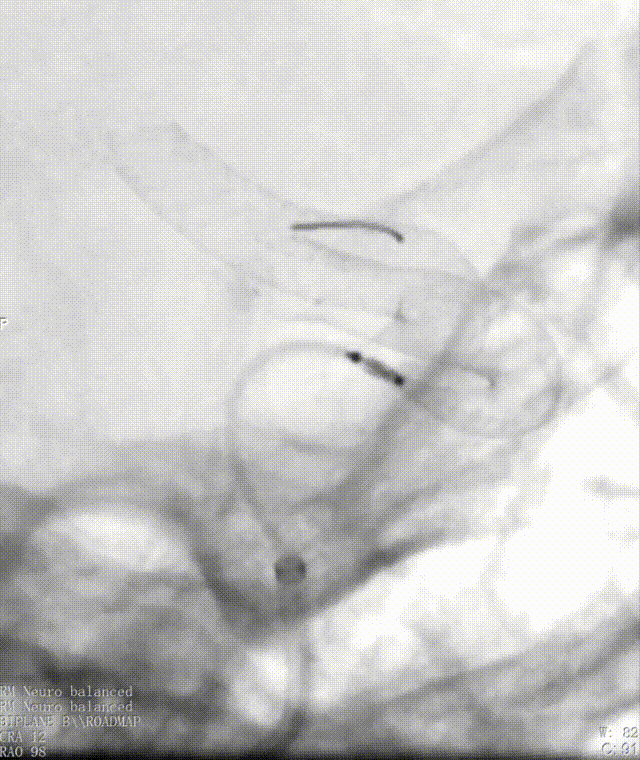

迂曲段通桥麒麟™血流导向密网支架释放过程。

支架twist或打开不良处理。